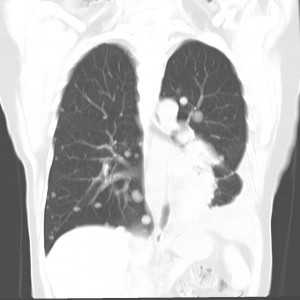

Компьютерная томография — один из самых чувствительных и распространенных методов диагностики метастазов в легкие. Это исследование позволяет выявить очаги опухоли меньше 1 мм в диаметре. Более чувствительным и специфичным методом является только ПЭТ/КТ, но он меньше распространен, дороже и сложнее в применении.Для выявления мелких очагов лучше использовать спиральную компьютерную томографию. Чтобы определить метастазы в легкие, контрастное усиление не является обязательным, но может быть полезным для дифференцировки легочных сосудов и лимфоузлов при их вторичном поражении.

Множественные гематогенные вторичные узлы при раке почки, компьютерная томография (КТ).